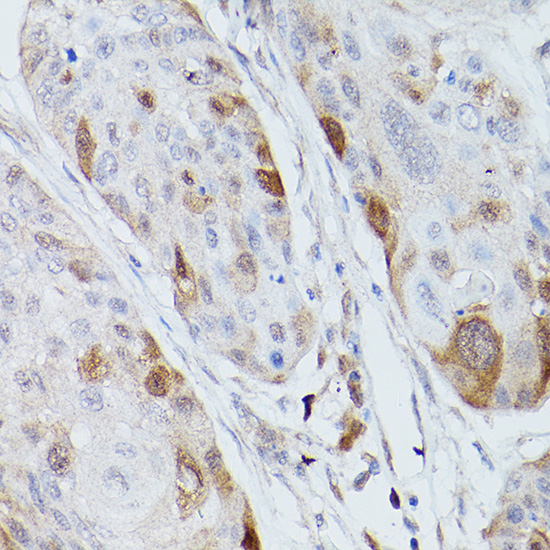

Immunohistochemistry of paraffin-embedded human colon carcinoma using UBE2C Rabbit pAb.

Immunohistochemistry of paraffin-embedded human esophageal cancer using UBE2C Rabbit pAb.